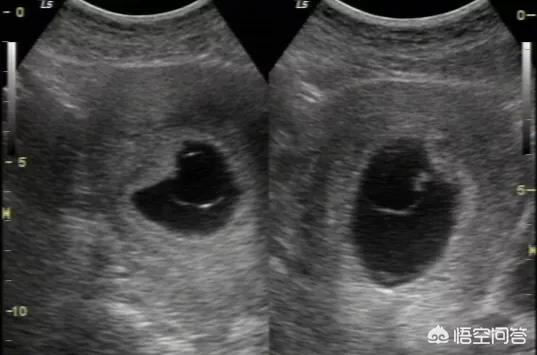

如果出现hCG值不增反降,或者是hCG已经很高,却复查多次超声都没有看到原始心管搏动,那么考虑胚胎停止发育,应当要及时终止妊娠。

很多宝妈都经历过这种情况,有孕囊但是就是迟迟不出现心搏,这种情况叫做空卵,也就是种子有问题,是长不出胎心来的,所以在一定程度上讲胎心的出现才提示宝宝是存活了。

怀孕多长时间可以用B超查出有没有胎心,这个需要根据不同B超分别对待,阴道B超较腹部B超可以更早的发现胎心,但是国人往往对阴道B超存在敌意,一般做的都是腹超,腹部B超一般在孕5周是出现孕囊,孕6周左右出现胚芽及心搏,晚点的需要孕7-8周。这个具体存在差异性,尤其是那些月经不规则的宝妈们,正常情况下孕囊出现后2-3周出现心搏,不能按常规的停经时间计算。

总结,正常情况下孕6-7周行腹部B超可以查出胎心,太早查B超往往只能可见一个孕囊。个人建议没有异常情况,孕7-8周行B超检查,如果存在胎心,建议同时建卡。祝好孕。